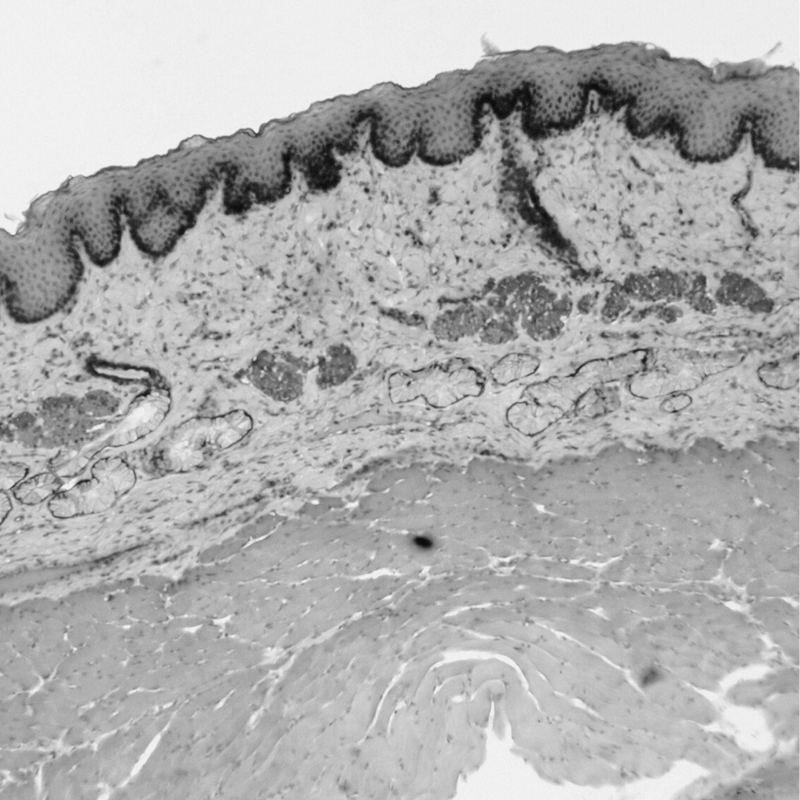

L’aloe vera est réputé pour ses puissantes propriétés hydratantes, faisant de lui un ingrédient de choix pour les soins de la peau. Riche en eau (à plus de 95 %), son gel agit comme un véritable réservoir d'hydratation. Cette teneur élevée en eau est associée à une structure unique de polysaccharides, qui permet à l’aloe vera de retenir l’humidité et de former un film protecteur à la surface de la peau. Ce film agit comme une barrière qui limite la perte d'eau transépidermique, conservant ainsi l'hydratation plus longtemps.

L’effet hydratant de l’aloe vera ne se limite pas seulement à la surface de la peau. En pénétrant les premières couches de l’épiderme, il aide à nourrir les cellules et à maintenir l'équilibre hydrique de la peau en profondeur. Utilisé régulièrement, l'aloe vera contribue ainsi à une peau plus lisse, rebondie et lumineuse, tout en renforçant la barrière cutanée pour mieux résister aux agressions extérieures.